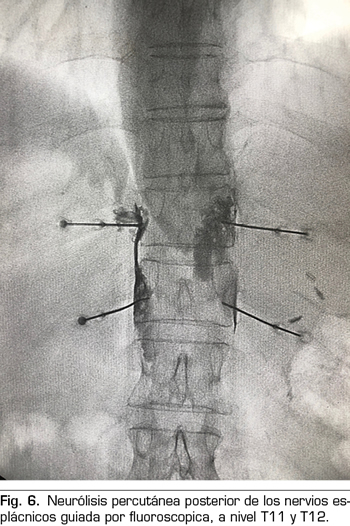

Técnica percutánea

Se realiza mediante un abordaje posterior retrocrural, normalmente guiado por fluoroscopia (Figura 6). Las lesiones pueden llevarse a cabo mediante radiofrecuencia convencional o utilizando agentes neurolíticos como en el plexo celiaco.

Radiofrecuencia convencional o térmica de los nervios esplácnicos

Consiste en la producción de una corriente eléctrica de alta frecuencia en la punta de la aguja, generándose calor alrededor de esta y llegando a producir una destrucción tisular si se sobrepasan los 45-50 °C y los 20 segundos de estabilización de la temperatura, influido también por otros factores como el calibre de la aguja y la longitud de la punta activa (50). Para los nervios esplácnicos se suelen utilizar agujas de 18 a 20 G, con una punta activa mínima de 10 milímetros, estableciendo lesiones de 80 °C y 90 segundos por aguja (51).

La radiofrecuencia convencional de los nervios esplácnicos está ampliamente documentada en la literatura con estudios que han demostrado su eficacia en el dolor asociado a la pancreatitis crónica, pero no en el cáncer de páncreas. Esto es debido a la radioanatomía más predecible de los nervios esplácnicos y a la menor tasa de complicaciones severas, ya que la técnica permite una estimulación sensitiva y motora previa para evitar la lesión de otros nervios, y no precisa necesariamente de agentes neurolíticos que puedan difundir y afectar otras estructuras (51,52). Respecto al cáncer de páncreas, hay un estudio retrospectivo de 56 pacientes que muestra un descenso significativo de la escala visual analógica (EVA) y del consumo de opioides, con una mejoría en la calidad de vida de los pacientes de hasta seis meses de duración, pudiendo ser más prolongado el efecto que con el uso de agentes neurolíticos (53). No obstante, son necesarios estudios controlados y aleatorizados para llegar a obtener conclusiones relevantes.

Neurólisis química de los nervios esplácnicos

Recientemente, la administración de agentes neurolíticos en los nervios esplácnicos ha vuelto a ganar interés debido a su menor variabilidad anatómica en relación a estructuras circundantes y a su mayor accesibilidad percutánea (54-56). No obstante, hasta ahora no hay una evidencia superior de la neurólisis química frente a la radiofrecuencia convencional en los pacientes con cáncer de páncreas.

Las complicaciones en el abordaje de los nervios esplácnicos son infrecuentes. Al igual que los bloqueos neurolíticos, la radiofrecuencia también puede producir neuritis que suele desaparecer a las pocas semanas. La hipotensión y la diarrea son autolimitadas y se derivan de la simpaticólisis, aunque con menor frecuencia que con el bloqueo del plexo celiaco. Como en todos los procedimientos torácicos, hay que estar alerta del posible neumotórax, recomendándose un control radiográfico posterior. La sensación de disnea que a veces presentan los pacientes puede ser debida al bloqueo anestésico del nervio frénico, produciéndose una elevación del hemidiafragma. Otras complicaciones raras reportadas en la literatura son la lesión del ductus torácico, sospechosa cuando se aspira fluido amarillento y turbio a través de la aguja, o la inyección intradiscal e intravascular, que siempre debe ser verificada previamente con contraste radiopaco. Las parestesias pueden aparecer si hay contacto de la aguja con las raíces dorsales torácicas (58). El uso de radiofrecuencia en los nervios esplácnicos debería evitar el riesgo de paraplejia (51), pero los resultados han sido poco estudiados.